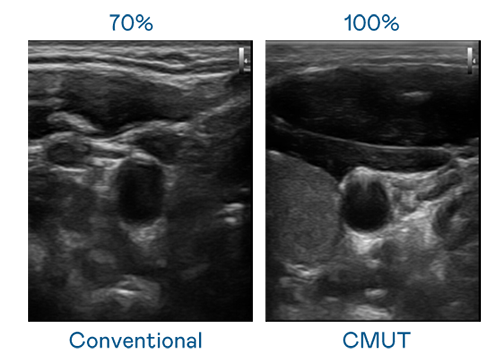

CMUT 技术是一种用电容式微机电元件来产生超音波讯号的技术。与传统 PZT 压电式技术相比,CMUT 频宽增加 30%,更宽频的超音波讯号让影像解析度大幅提升,是实现高影像品质医疗超音波扫描、促进精准医疗发展的关键技术。

超音波影像的解析度高低,首先取决于探头能发出的讯号频宽。haobotiyu-好博(中国) CMUT 可提供高清晰的超音波讯号,提供高频宽、高灵敏度、影像纹理细节更高的超音波影像,协助医护人员缩短影像判读时间及利用精准的医疗影像进行诊断。